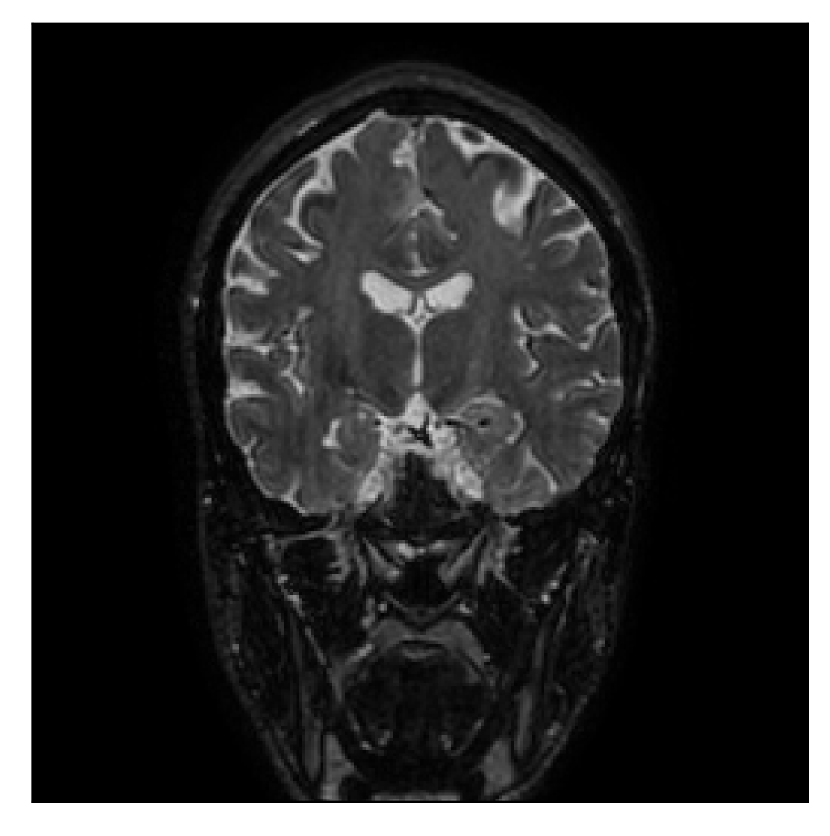

| Section 3.2, Figure 10 | Sagittal | 25.84 | 28.07 | 0.7032 | 0.8093 |

| Coronal | 26.35 | 30.40 | 0.7851 | 0.9021 | |

| Axial | 28.11 | 30.54 | 0.8248 | 0.9012 | |

| Section 3.2, Figure 10 | T1 | Completely corrected | Some blurring | No additional artifacts | Good grey white matter differentiation, |

| some loss of grey matter low signal | |||||

4.2 Experiment 2: choice of the reference contrast

With the experiment described in Section 3.2, we demonstrate the flexibility of the correction scheme with respect to the choice of the reference contrast. The results are shown in Figure 10. Contrary to the experiments detailed in the previous section, we are now considering a T2-weighted reference contrast to guide the correction of a T1-weighted corrupted contrast. The quality of the correction indicates that the proposed technique is rather flexible in terms of reference contrast.

Furthermore, the flexibility of the proposed motion-correction method is demonstrated with different combinations of motion-corrupted and reference contrasts (Section 4.2). Our experience suggests that an important factor in assessing the effectiveness of the reference contrast as a guide for motion correction lies in the similarity of the -space distribution of the two contrasts. Good reconstruction quality can be expected when the reference contrast has similar or higher frequency content when compared to the corrupted contrast, regardless of the type of contrast considered.

Coronal

Axial

Coronal detail